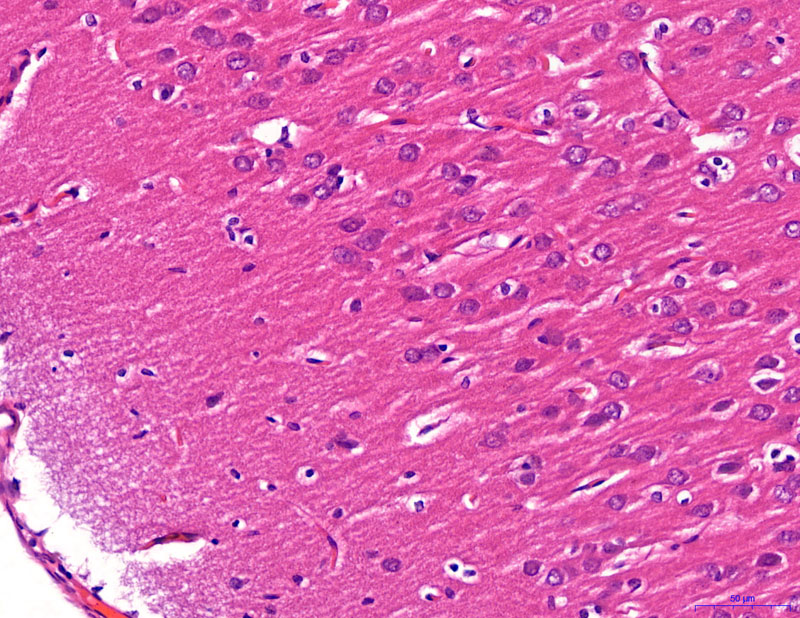

給藥-400

模型-400

正常-400